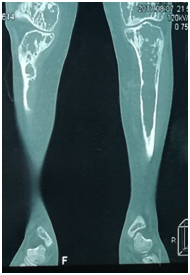

Chest Multi-Slice CTscan revealed several diffused interstitial reticular densities in both pulmonary fields with small nodular densities without enlargement of lymphatic nodes (Figure 3). Pelvis Multi-Slice CT scan revealed lytic lesions in hip and legs without invasion of adjacent tissues (Figure 4). We sent the Bronchial incisional biopsy taken by bronchoscopy and surgical incisional biopsy taken from left tibia to pathology department.

Figure 4 Pelvis Multi-Slice CT scan revealed lytic lesions in hip and legs without invasion of adjacent tissues.

There is bone involvement in 78% of patients with LCH. Bone involvement is usually in the flat bones, with lesions of the skull, pelvis, and ribs accounting for more than 50% of all lesions. The lesions can be painful or asymptomatic.4 In our case, the patient presented with pain and edema in both legs and inability to walk.

Radiographic features in bone LCH depends on site of involvement and phase of the disease. X-ray of the pelvic and legs showed lytic lesions. MS-CT scan of the pelvic and legs showed several generalized lytic lesions without infiltration to the near tissues. The biopsy from tibia confirmed LCH diagnosis.